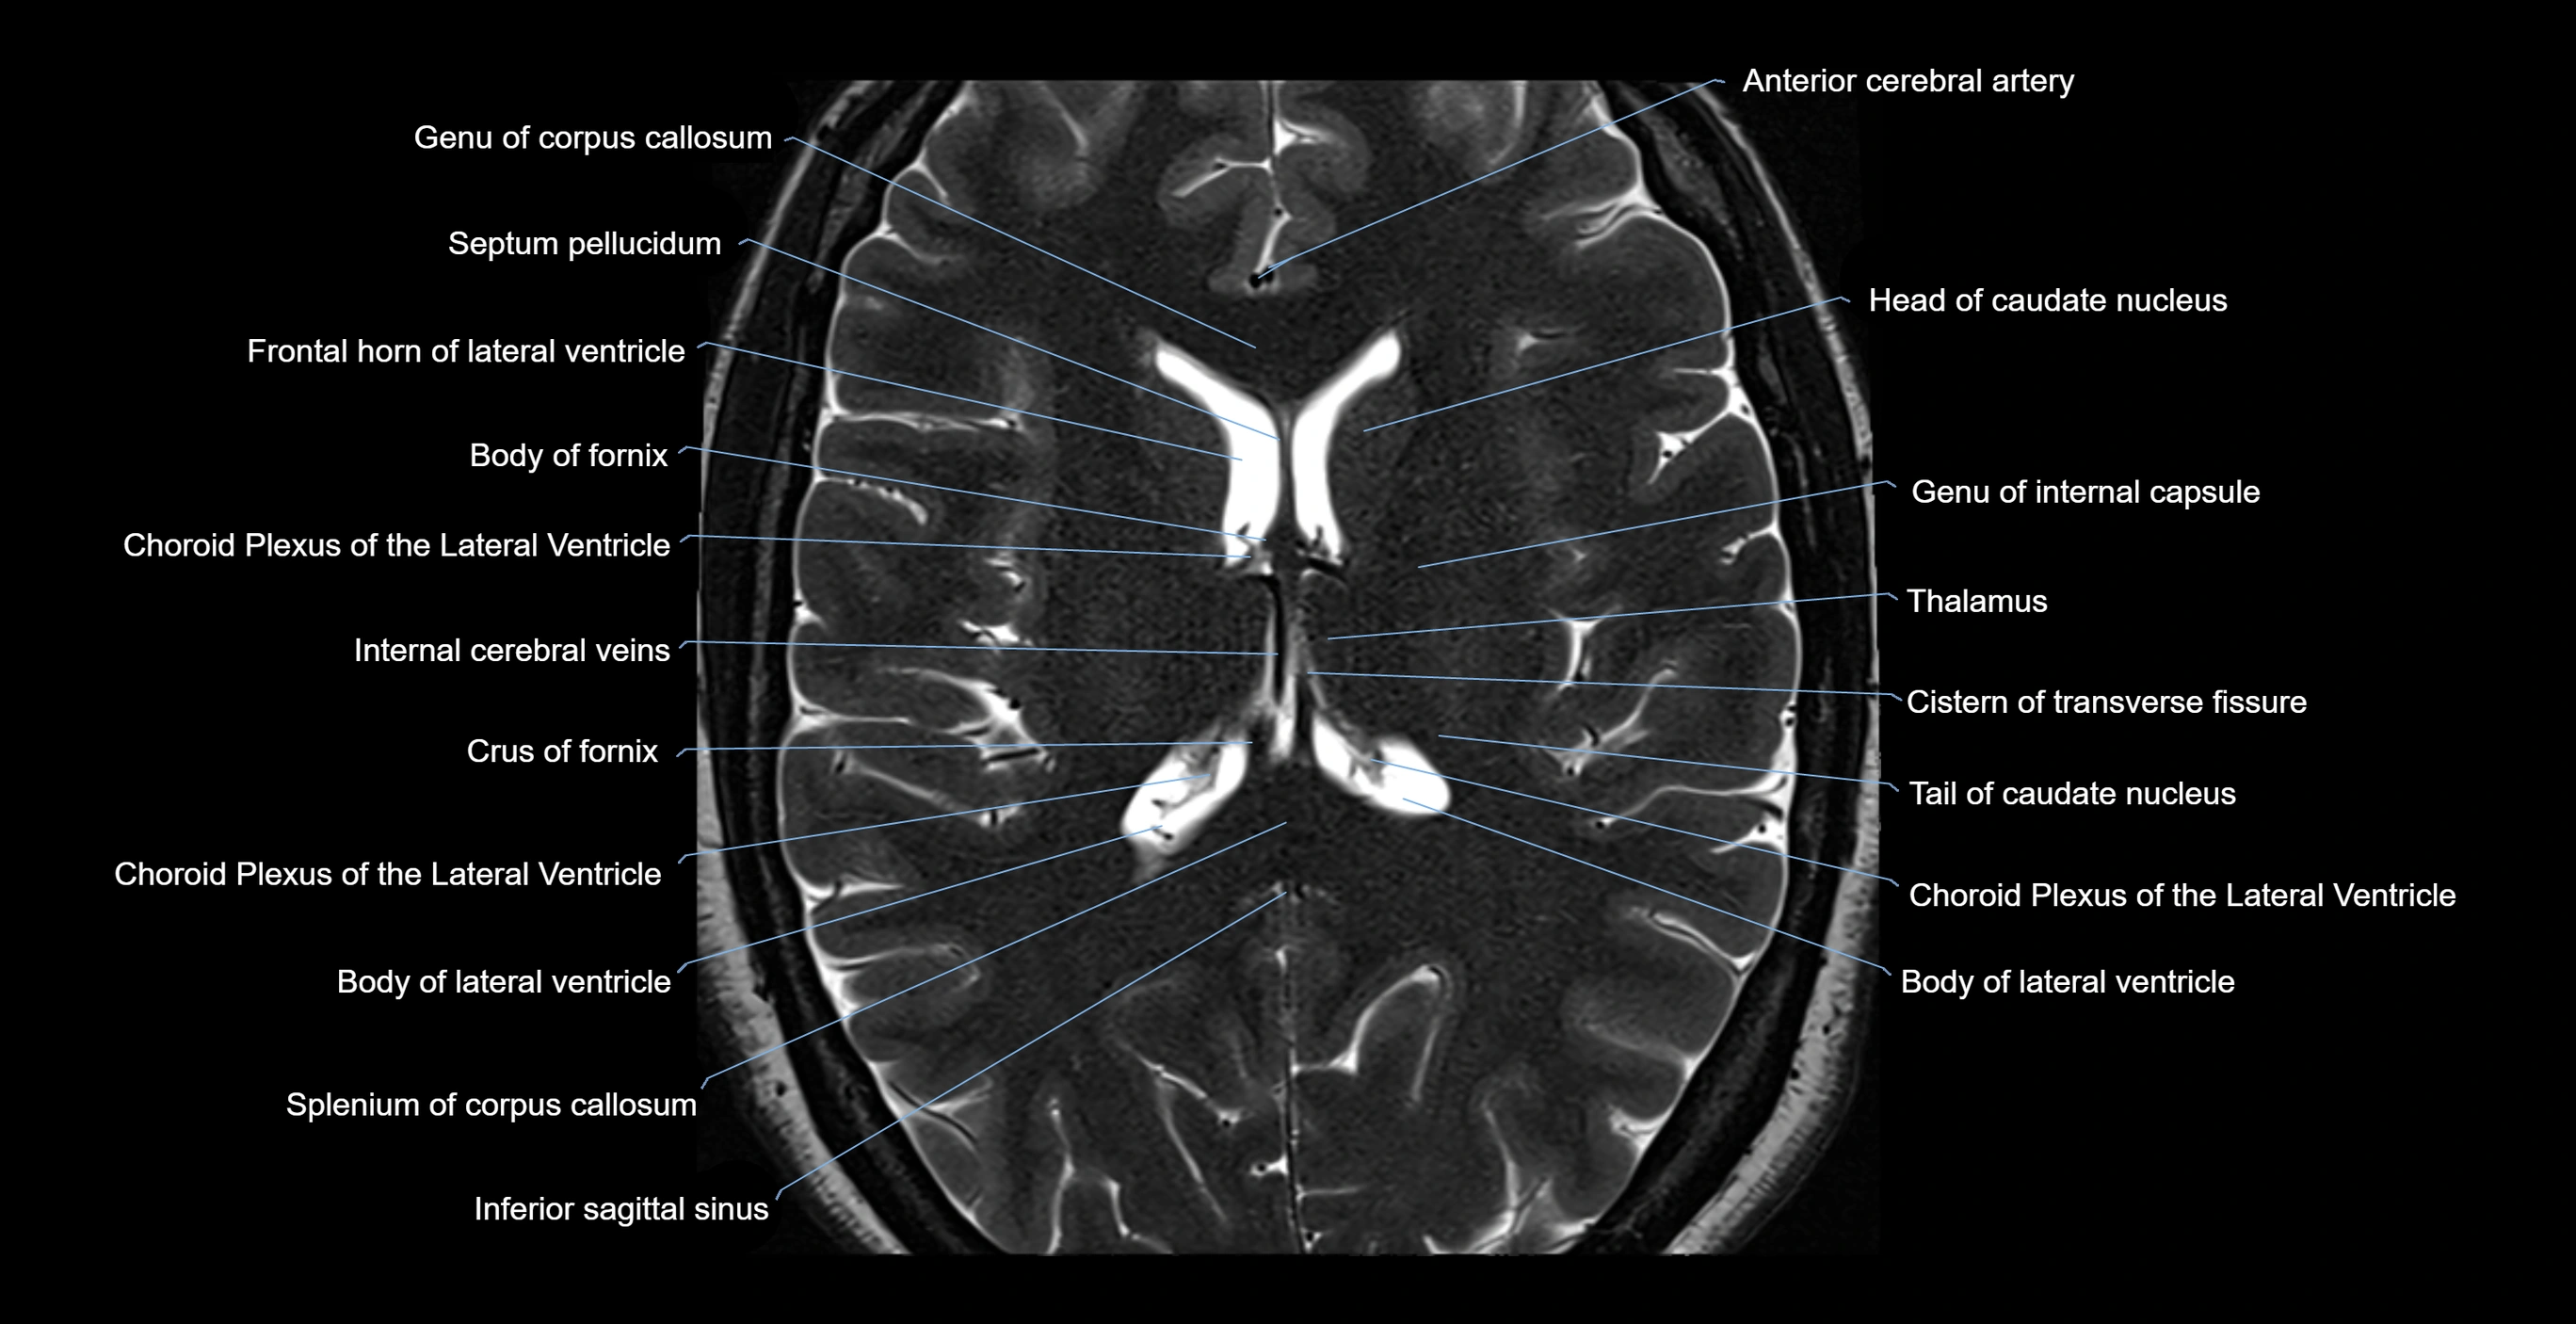

MRI images